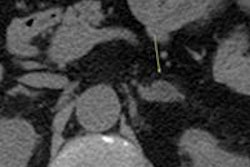

Adrenal incidentalomas are found in 5% to 10% of abdominal CT scans, which are performed in cases of other suspected abnormalities or conditions, such as adrenal adenoma. Fortunately for patients, most of these lesions are benign and not considered cancerous.

MRI is often used as a second option to determine etiology and provide additional diagnostic information on unknown masses. In particular, MR imaging sequences, such as fat saturation and T2-weighted imaging with or without contrast, help lead to a diagnosis.

Imaging findings sometimes lead to a more rare, but misleading, pathology of pheochromocytoma or to a suspected malignancy of corticosteroidal adenoma or a metastasis.